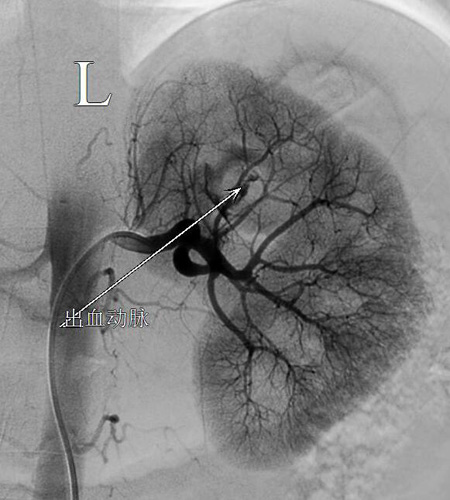

清晨6点25分,患者被送入介入手术室准备手术。当时患者神志不清,烦躁不安,引流出鲜红色血性尿。介入医学科为患者在局麻下穿刺右侧股动脉,行"左肾动脉造影+栓塞术”并栓塞止血成功。手术结束后,患者的尿色转为淡红色,转入重症医学科继续治疗。

急诊介入手术栓塞止血前后对比

据介绍,肾出血引起血尿若是诊断及治疗不及时,可危及患者生命,保守治疗效果不佳,而手术探查具有盲目性,且难度大、风险高,创伤重。近年来,随着介人放射学快速发展,介人治疗技术已应用到急救医学领域,并发挥着极其重要的作用,此项技术具备诊断和治疗两种功能,使得动脉性出血的急诊(症)患者能够得到快速的诊断和治疗,该患者的生命能够得以挽回并最终保住左肾,介入"肾动脉造影+栓塞术”起到了关键性作用。(介入医学科 黄玉)